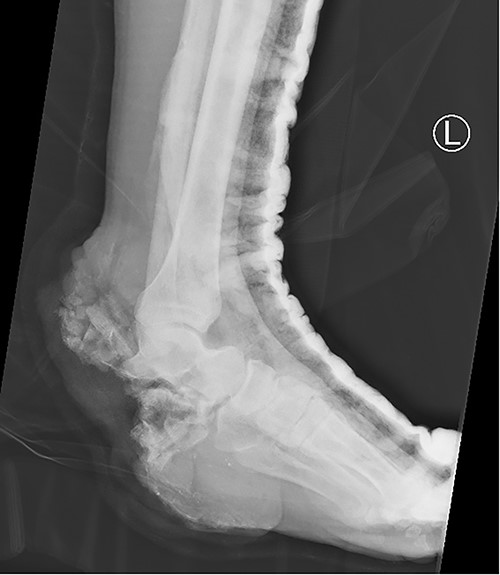

A 32-year-old male, without any known medical illnesses, presented after sustaining a blast injury to the left foot by a landmine. Upon presentation the patient was hemodynamically stable, with isolated large left hindfoot defect associated with exposed vital structures (talonavicular joint, tibial nerve and posterior tibial artery and vein), both tibial nerve and posterior tibial artery and vein where intact with intact sensation over the remaining skin of the foot; (Fig. 1). X-ray showed total calcaneus bone loss (Fig. 2), computed tomography angiogram showed intact anterior and posterior tibial arteries, fractured talus and complete loss of calcaneus bone.

X-ray of the left foot showing complete loss of the calcaneus bone.